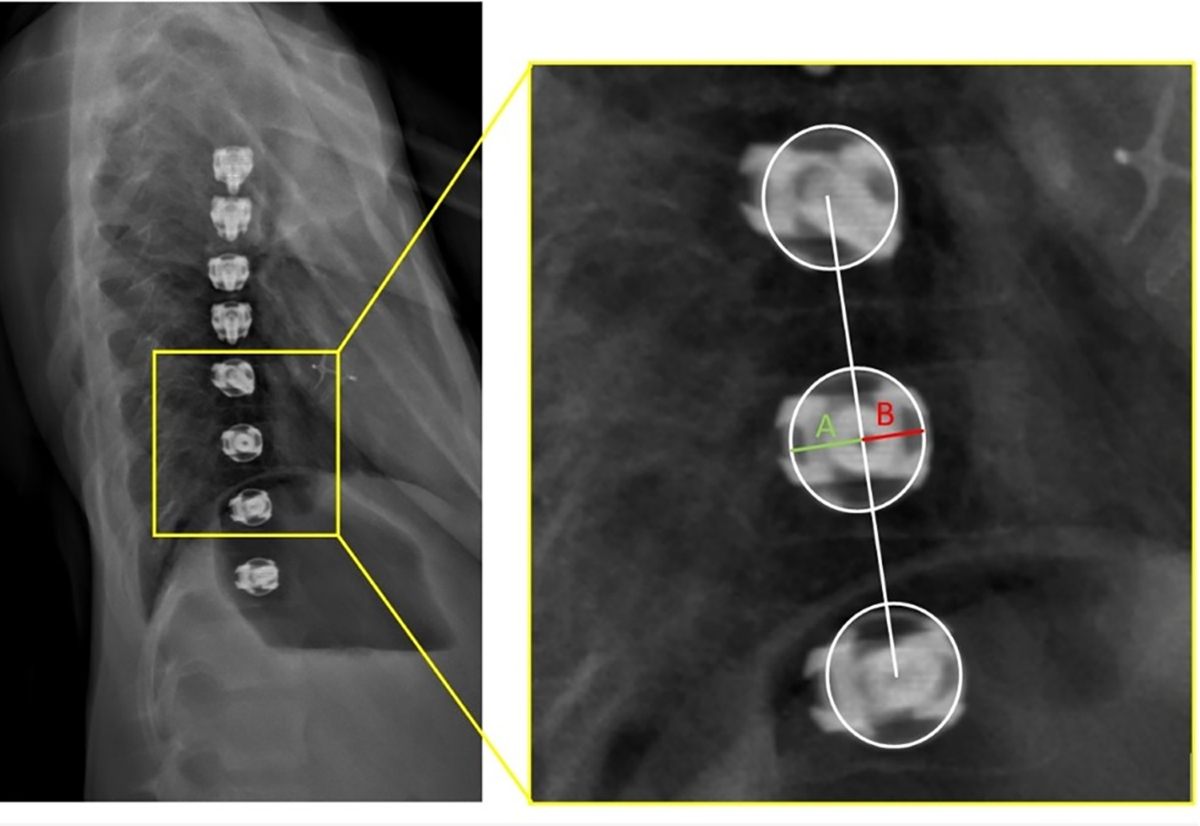

Inter-screw index as a novel diagnostic indicator of tether breakage |  Spine Deformity

Automated measurements of interscrew angles in vertebral body tethering  patients with deep learning - The Spine Journal

PDF) Inter-screw index as a novel diagnostic indicator of tether breakage

Inter-screw index as a novel diagnostic indicator of tether breakage

Does screw alignment affect tether breakage in vertebral body tethering? |  European Spine Journal | Springer Nature Link